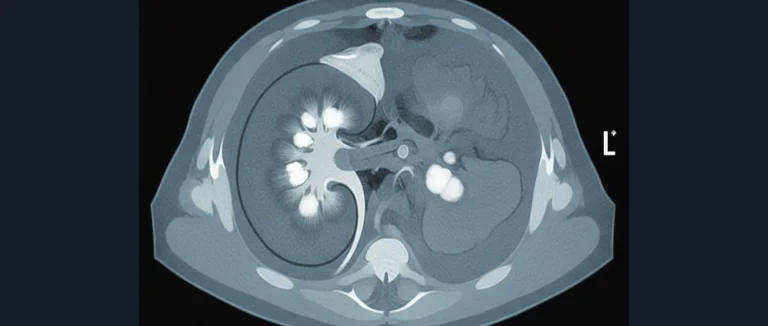

Компьютерная томография (КТ) в оценке почечных камней

КТ с контрастированием считается золотым стандартом в визуализации почечных камней, особенно при необходимости точного определения размера, формы и плотности конкрементов. Современные многослойные сканеры позволяют получать тонкие срезы (0,5‑1 мм), что улучшает визуализацию даже мелких камней.

Ключевые параметры КТ‑сканирования:

| Параметр | Значение |

|---|---|

| КТ без контраста | Определение плотности камня (Hounsfield Units) |

| КТ с контрастом | Оценка сосудистой анатомии и исключение опухолей |

| 3‑D реконструкция | Визуализация пути удаления камня |

Преимущества КТ:

- Высокая чувствительность (более 95 % для камней любого размера).

- Точная локализация в почечной системе и мочеточнике.

- Оценка плотности камня, важная для выбора метода разрушения (например, литотрипсия).

Недостатки включают облучение (около 5‑10 мСв) и необходимость контроля функции почек при использовании контрастных веществ. При аллергии на йодные контрасты предпочтительнее безконтрастный протокол или МРТ.